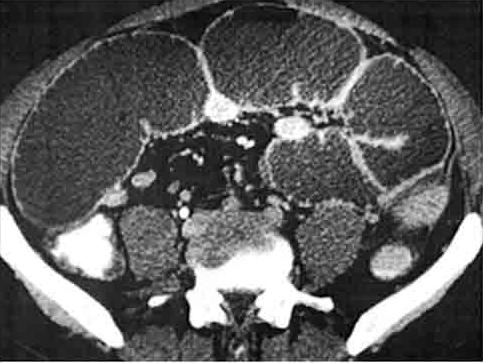

La vue coronale

de TDM montrant la cause de l'invagination : Lipome

du grele de grand diametre

| Image TDM en coupe axiale : Invagination

ileo- colique |